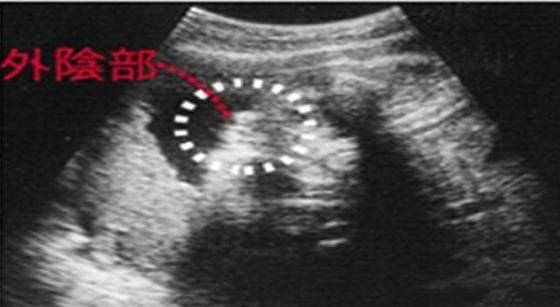

关于四维彩超看男女的说法,在众妈妈“群”里早就流传着一个说法,孕早期看孕囊形状可以看性别:像茄子或长条状的是男宝宝可能性大(椭圆形),圆

四维彩超看男女的诀窍 四维彩超怎么看男女教你另辟蹊径看胎儿性别 大家都知道四维彩超是可以检查出胎儿性别的,但因为国家明文规定不能查胎儿性别,所以医生也不会透露